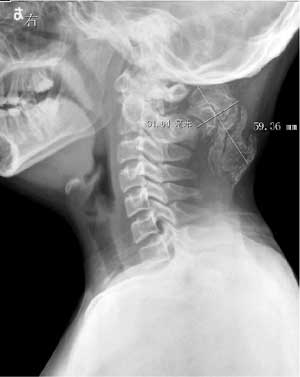

以下是引用向医生在2004-6-27 8:13:44的发言:[br]颈后部巨大肿块,内有多量钙化及骨化影,肿块与枢椎棘突似有薄蒂相连.[br]意见:颈后部肿块考虑以枢椎外生软骨瘤可能性大,其次考虑骨外软骨瘤.

以下是引用曼一拍在2004-6-30 23:46:56的发言:[br]抄书:进行性骨化性肌炎也叫进行性骨化性纤维发育不良。是一种少见的遗传性发育不良(多为常染色体显性遗传),先天性骨异常合并严重进行性的软组织骨化。病因不明,无有效治疗方法。[br]临床可有:耳聋.脱发.智力迟钝.骨骼畸形和关节活动受限。[br]x线表现:1. 软组织骨化:出生一月可有,骨化多自项韧带或胸锁乳突肌开始。进行性,直至20-30岁全身大部分结缔组织和肌肉都发生骨化,脊柱和大关节僵直。2.骨骼异常:主要在手和足的拇,以拇趾短为主,且有先性拇外翻。3.关节改变:长骨干骺异常,关节半脱位等。[br] 故,我支持向医生。